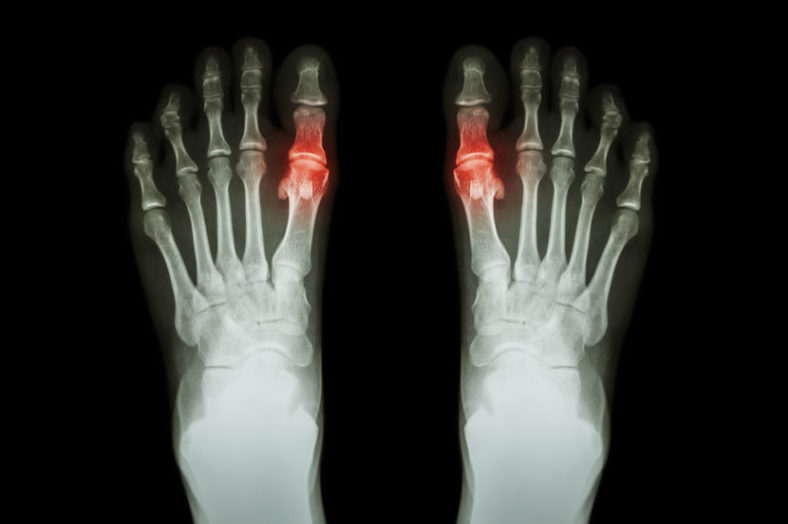

Man Hospitalized for Gout Flare After Just Thinking About Steak

ATLANTA, GA – A massive sign that his gout is poorly controlled, area 56-year-old ...